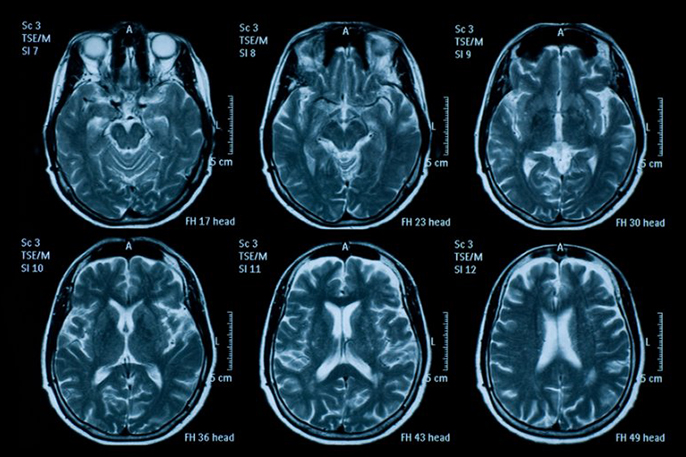

- Speed the diagnosis of traumatic brain injury, stroke or aneurysm by applying state-of-the-art artificial intelligence technology to computed tomography (CT) scanning (principal investigator: Pratik Mukherjee, UC San Francisco).